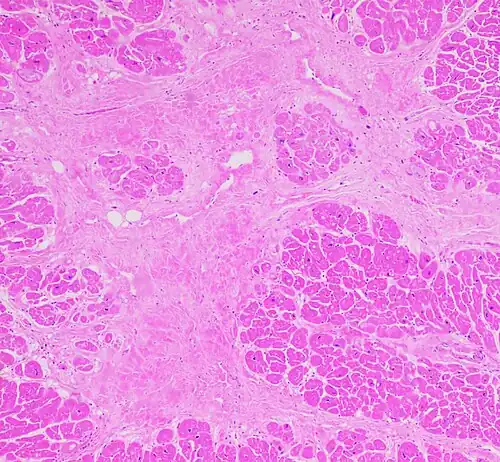

Interstitial fibrosis of chronic ischemic heart disease, H&E stain, with associated relatively well organized myocardial bundles -